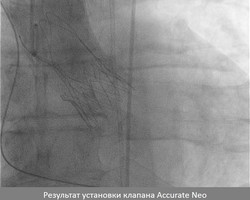

Для выполнения TAVI и обеспечения защиты головного мозга использовалась миниинвазивная техника. Операция выполнена под местной анестезией, без использования общего наркоза. Клапан устанавливался через бедренную артерию, а устройства защиты – через левую и правую лучевые артерии. Слаженная работа сотрудников отдела рентгенэндоваскулярных методов диагностики и лечения и блока интенсивного наблюдения позволила максимально облегчить вмешательство для больного, а также повысить его эффективность и безопасность. Уже на следующие сутки после операции пациент отметил значительное улучшение самочувствия и отсутствие одышки. Неврологический статус полностью сохранен.